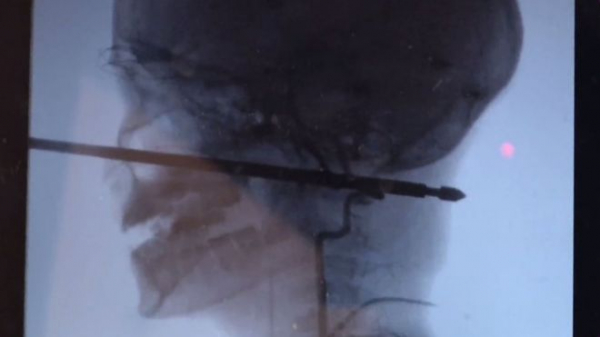

Мальчик играл в доме, закрепленном на стволах деревьев, когда на него напали осы. Он свалился с высоты чуть более метра и приземлился прямо на 30-сантиметровый металлический шампур для приготовления шашлыков. Шампур пронзил череп и погрузился в ткани головы на 15 сантиметров. К счастью, чудесным образом металлическая палка вошла в голову, миновав и глаза, и мозг, и спинной мозг, и крупные кровеносные сосуды.

Рентгеновский снимок показывает, как шампур пронзил голову мальчика. Фото: CBS

Так как из раны не было активного кровотечения и шампур не повредил жизненно важные органы, врачи успешно удалили квадратный стержень. Операция была очень сложной именно из-за формы шампура с острыми краями и длилась несколько часов.

Коджи Эберсоул, директор отделения эндоваскулярной нейрохирургии больницы Университета Канзаса сказал Kansas City Star, что самую большую сложность для хирургов при удалении шампура представляли кровеносные сосуды на шее мальчика. Врач назвал чудом то, что при такой сквозной травме шампур не повредил ничего в голове потерпевшего роковым образом.